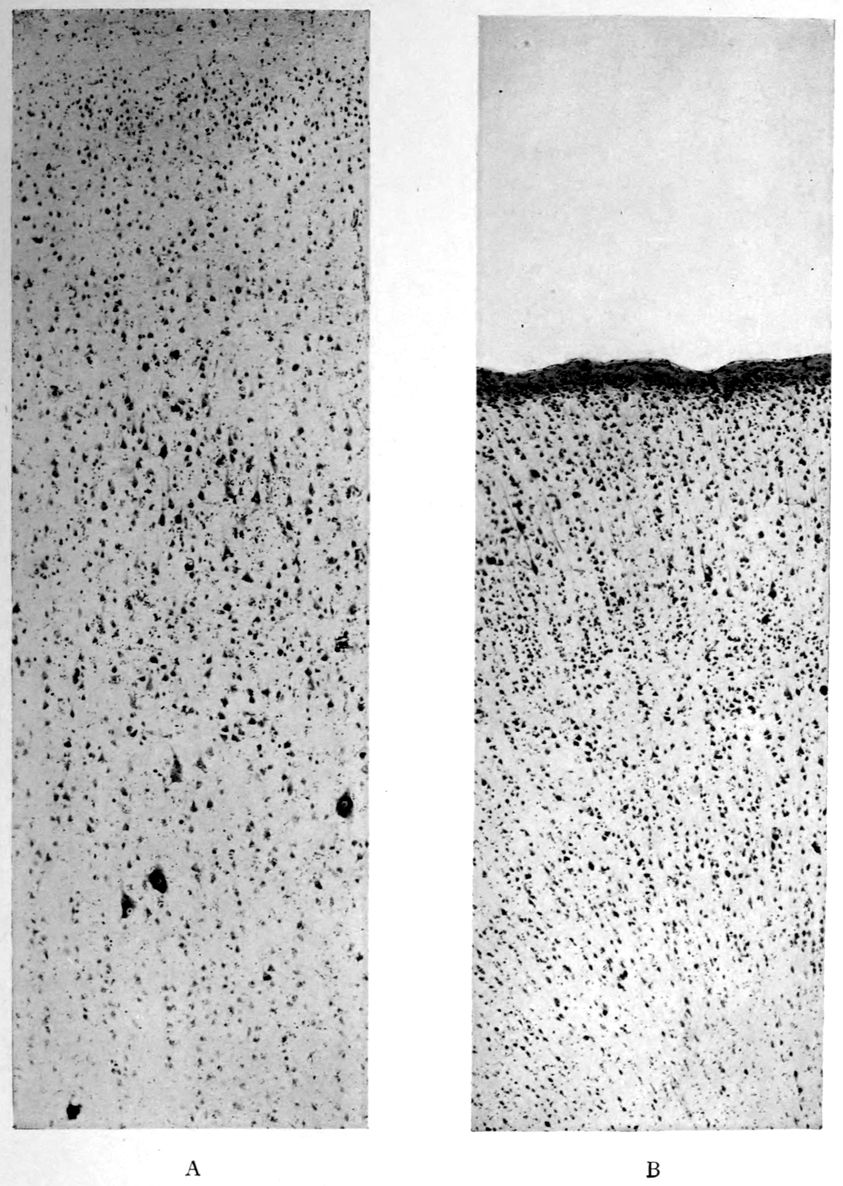

A. Normal postcentral cortex. (Compare B.)

B. Nerve cell losses. Perivascular deposits of mononuclear cells, amongst which are numerous plasma cells. Note decrease in number of nerve cells. Note irregular disposition of nerve cells. From paretic neurosyphilis.

Microscopic findings are here presented merely in sufficient detail to establish the diagnosis. The left superior frontal gyrus shows extensive and somewhat irregular cellular and fibrillar gliosis of the plexiform layer, together with an increase of thickened vessels having lymphocytes and plasma cells in their sheaths.

The perivascular infiltrations are most extensive in the lower layers of the cortex. The lamination is in places thoroughly obscured, except that representatives of the layer of large external pyramids are almost always demonstrable.

The layer of medium-sized pyramids has undergone more numerical loss of elements than have the other layers.

Gliosis of white matter.

Specimens from the cerebellum show a destructive process of great severity, but a little irregular in extent, affecting chiefly the Purkinje cell belt. The Purkinje cells are often absent throughout one side of a given lamina, and there has ensued a dense accumulation of neuroglia cells along a former Purkinje cell belt, together with a considerable gliosis of the molecular layer. Considerable gliosis of the white matter, both diffuse and perivascular in distribution.

Perivascular plasma cell infiltrations as in cerebrum, but largely meningeal or in the white matter.

Sections from the corpora striata demonstrate a mild and early granular ependymitis, considerable subependymal gliosis of cellular type, considerable perivascular gliosis in the white portions of the tissue, and a moderate infiltration of perivascular sheaths with pigmented cells, lymphocytes, and plasma cells. There is little evidence of alteration in the nerve cells. Some are unevenly pigmented.

41Characteristic and constant in paretic neurosyphilis is the Plasmocytosis and Lymphocytosis, Perivascular in distribution about small cortical vessels. There is also a characteristic (though characteristically less prominent) Plasmocytosis and Lymphocytosis, Meningeal in distribution. The pleocytosis of the spinal fluid, almost constant though variable in amount in life, is an indicator of the meningeal picture and less directly of the parenchymatous picture.

Granular Ependymitis (“sanding” of ventricle floors) is characteristic and may be regarded as part of the parenchymatous picture. This ependymitis is an indicator how chemical changes could be readily produced at least in the ventricular fluids, since the limiting membranes of the nerve tissue are here subject to multiple breaks. The “sanding” is a neuroglia reaction to these multiple small breaks (Weigert’s explanation).

Parenchymatous losses have led to Atrophy and Sclerosis, of very varying extent in different parts of the encephalon. The atrophy is characteristic in paretic neurosyphilis, but by no means constant. Numerous cases have come to autopsy without clearly defined gross atrophy. Sclerosis is also characteristic and even more frequent than atrophy, doubtless because sclerosis represents an earlier phase of a process eventuating in gross atrophy.

A Tabetiform Picture characterizes the spinal cord, but in this case the tabetic clinical picture did not precede the paretic clinical picture. We are consequently to regard the tabetic spinal process as incidental and on all fours with the Cerebellar and Pontine Atrophy.